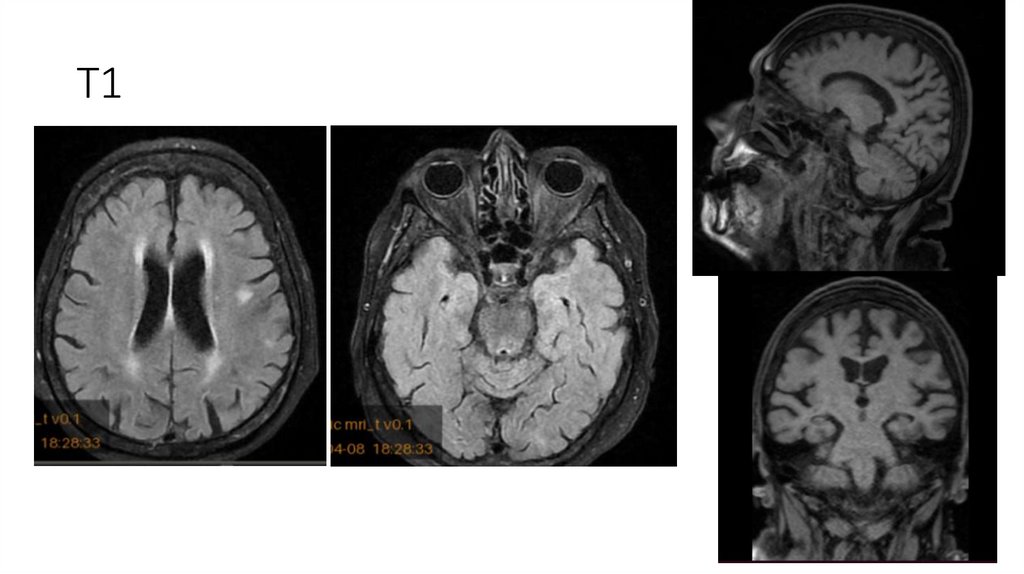

18. МРТ ГМ от 08.04.2025

Описание

-Срединные структуры не смещены.

-Желудочки обычной формы и размеров.

-Субарахноидальные пространства не расширены.

-Дифференциация серого и белого вещества сохранена.

-В белом веществе головного мозга, в паравентрикулярных и конвекситальных областях визуализируются множественные очаги

диаметрами 3-10мм, вероятно, сосудистого генеза.

-Отмечается незначительное расширение периваскулярных пространств.

-МР-сигнал от подкорковых ядер не изменен.

-Селлярная область без патологических изменений.

-Размеры гипофиза в пределах нормы.

-Стволовые структуры и мозжечок в пределах нормы.

-Мостомозжечковые углы без особенностей.

-Краниовертебральный переход не изменен.

-Придаточные пазухи и ячейки сосцевидных отростков воздушны.

-Содержимое глазниц без особенностей. ;

Заключение

• МР-картина множественных очагов в белом веществе головного мозга, вероятно,

сосудистого генеза.

19. T1